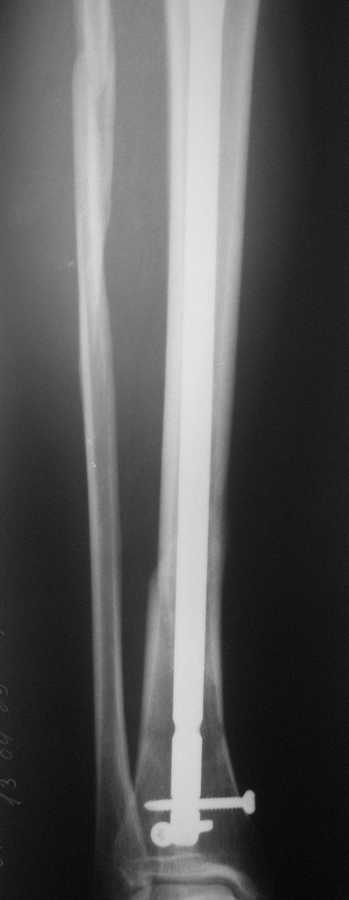

В январе 2009 года нами оперирована пациентка с переломом н\3 голени штифтом Expert. Динамизация через 4 месяца, пациентка при этом уже ходила с тростью. Дома периодически передвигалась без дополнительной опоры. В настоящее время - через 9 месяцев с момента операции периодически в вечернее время беспокоят ноющие боли в места перелома (не постоянно). При беседе выяснено, что боли чаще беспокоят после того, как днем она походит по дому без трости. Пальпаторно по гребню берцовой кости болей нет, но по задне-внутренней поверхности б\б кости пальпирутеся западение на уровне места перелома.В чем ошибка??? и что делать???

Недостаточная стабильность. Не использованы все возможности дистального запирания, нет самого проксимального из дистальных винтов. Два винта из трех коротковаты. В результате при диинамизации появился диастаз.

Тут есть уже опасность перелома стержня по ближайшему к перелому отверстию. Так что правильнее сделать реостеосинтез с рассверливанием. При введении гвоздя в дистальный отломок использовать отклоняющую спицу

или винт, чтобы стержень оказался не у переднего кортекса, как сейчас, а где и надо - посередине. Это обеспечит еще и встречно-боковую компрессию.

Да, динамизация поздновата. Да дистальный отломок заперт одним винтом, два другие короткие, еще дно отверстие пустое...

Этот 9-ти мм. стержень ExpertTN вряд ли скоро сломается, если, конечно же, пациентка не имеет большого веса (>100 kg). Перештифтовать более толстым штифтом с рассверливанием, пожалуй, самый надежный вариант, но не факт, что единственный. Вполне правомочно подумать просто о косой остеотомии малоберцоыой кости (зачем резекция???) в средней 1/3 и попытке дополнительной стабилизации дистального отломка путем запирания штифта через свободное отверстие (наиболее проксимальное из дистальных) и замены двух самых дистальных винтов, причем косой самый дистальный лучше провести в другой плоскости. Возможно этого будет вполне достаточно для сращения...а вот периодически возникающие боли могут и остаться(((

По снимку гвоздь сидит плотно в узкой части большеберцовой, а на периферии нестабильная блокировка. Динамизация работает в течение первых 8 недель.